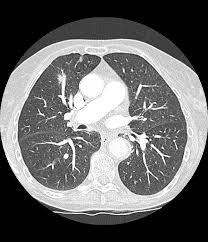

"폐결절(lung nodule)"은 폐 조직 내에서 직경 3cm 이하의 원형 또는 타원형 덩어리를 말합니다. 일반적으로 엑스레이나 CT 촬영에서 발견되며, 단독으로 존재하는 경우가 많지만 여러 개 나타날 수도 있습니다.

폐결절 진단은 주로 영상검사와 조직검사를 통해 이루어집니다.

- 영상 검사

- CT(컴퓨터단층촬영): 크기, 모양, 경계, 칼슘 침착 확인

- 추적 관찰

- 작은 결절(<8mm) 또는 악성 가능성이 낮은 경우

- 일정 기간 간격으로 CT 촬영하며 성장 속도 관찰